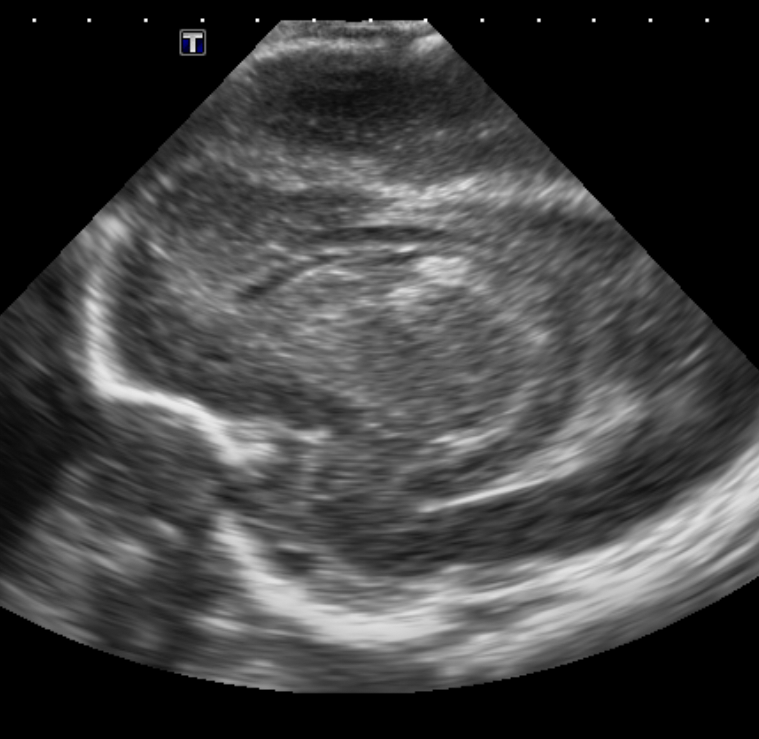

Brain

The brain is immature. [Yes/No]

There is under-sulcation and open sylvian fissures. [Yes/No]

There is/are multiple hypoechoic areas in the periventricular white matter. [Yes/No]

There is/are multiple hyperechoic areas in the periventricular white matter. [Yes/No]

There is diffuse cerebral edema with diffusely increased echogenicity of the brain parenchyma and loss of grey white matter differentiation. [Yes/No]

The thalami/basal ganglia are hypoechoic. [Yes/No]